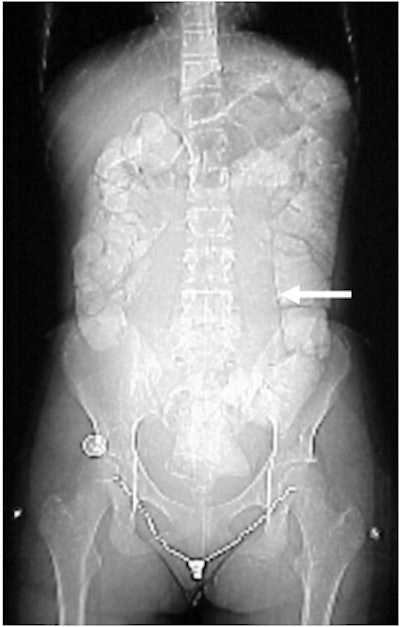

Case 1: The patient is a three-year-old black female who appears to be in no distress. The mother stated that she was giving the child a bath and noticed that her abdomen looked distended, and harder on the left side than the right. All the child’s labs are normal, and there is no family history of medical problems.

![]() |

| Figure CT 9 |

In Figure CT 9, the scout film shows a gaseous abdomen with displacement of bowel contents towards the right lower quadrant.